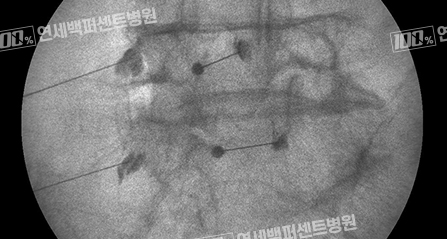

풍선 확장 경막외 신경성형술

꼬리뼈로 카테터를 삽입해 병변까지 도달시킨 뒤 카테터 끝에 달린 풍선을 확장해

협착부위를 넓히고 직접 염증 완화 및 유착방지 약물을 주입하는 시술입니다.

척추전방전위증

풍선확장술